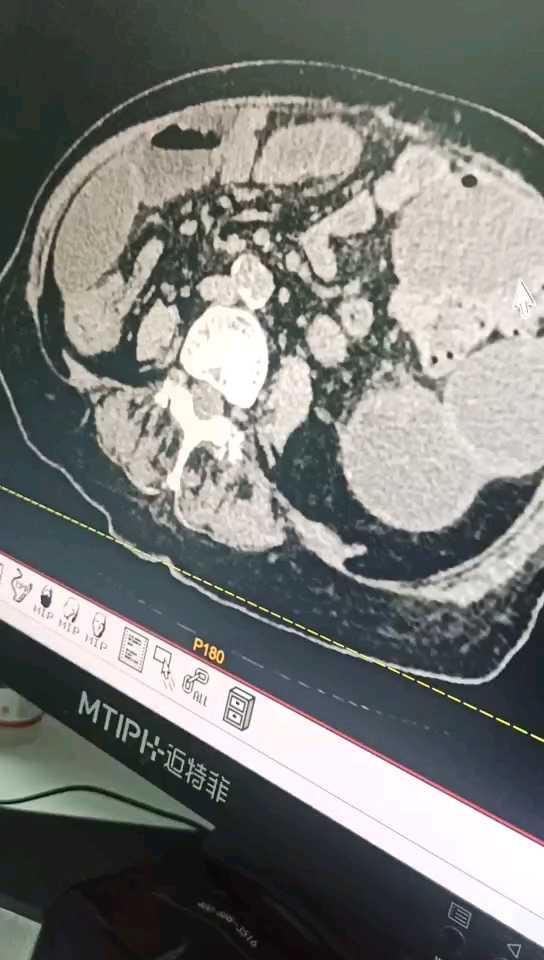

昨日我科会诊后急行全腹CT考虑小肠扭转